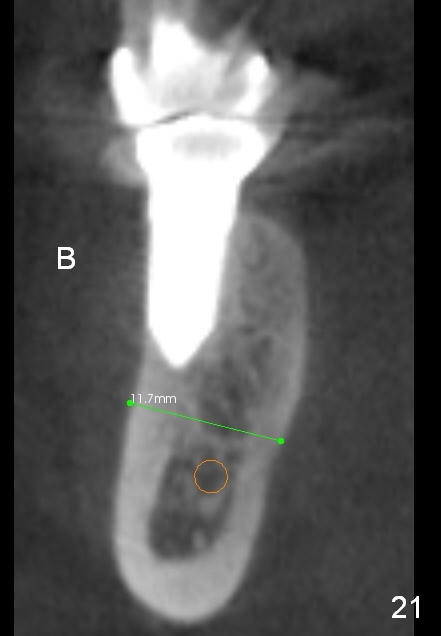

CBCT taken 15 months post cementation shows that the implant is buccally placed (Fig.21 B), associated with possible postop buccal plate resorption (as compared to Fig.23 (coronal section of the site of #19). The buccal plate is not only thinner than the lingual one, but also concave (Fig.22 <). The tooth center (i.e., septum; Fig.23 T) is more buccally located than the center of the basal bone (B). Considering the denser bone lingually, the initial osteotomy should be more lingually (^). If the implant develops infection, it will be replaced by a more lingually placed implant (Fig.24 green).